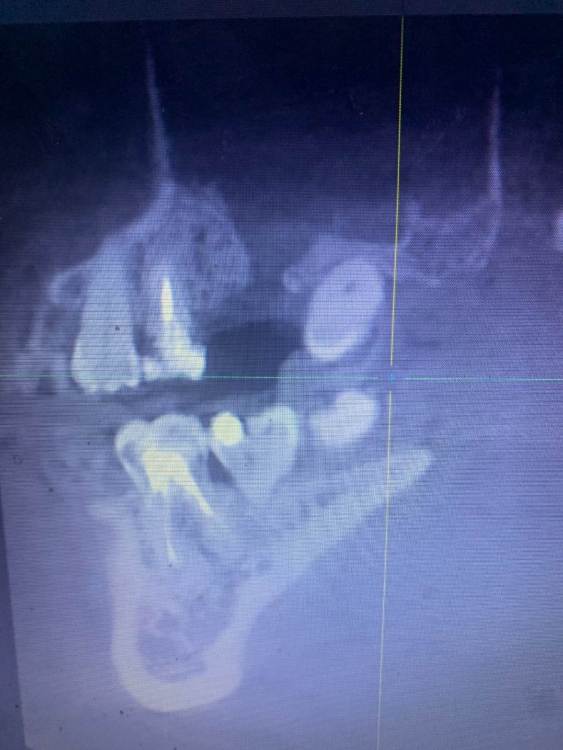

Екатерина А Опубликовано 16 февраля, 2024 Поделиться Опубликовано 16 февраля, 2024 Здравствуйте! Помогите пожалуйста советом. Было удаление 16 зуба с перфорацией пазухи, через месяц была радикальная гайморотомия с пластикой ороантрального свища. Прошло 5 месяцев, сделала КТ прицельное для имплантации зуба, столкнулись с отсутствием кости. Возможен ли синус-лифтинг в моей ситуации? Или что возможно сделать? Почему кость не срослась? Ссылка на комментарий

Irouil Опубликовано 17 февраля, 2024 Поделиться Опубликовано 17 февраля, 2024 Пазух у носа много, а на этом видны только гайморовы и те - частично Надо провести костную пластику этого сегмента альвеолярного гребня, через 4-9 месяцев (в зависимости от используемого метода) имплантация, судьбу соседнего зуба должен решать эндодонт (стоматолог терапевт, который лечит каналы), а не имплантолог Ссылка на комментарий

Irouil Опубликовано 18 февраля, 2024 Поделиться Опубликовано 18 февраля, 2024 @Екатерина А синус-лифтинг, но в Вашем случае скорее всего придётся его немного дополнить/усложнить. В любом случае - не рядовой синус-лифтинг. Сначала надо диагностику завершить, то самое КТ черепа, о котором говорил коллега @red_butler выше 1 1 Ссылка на комментарий